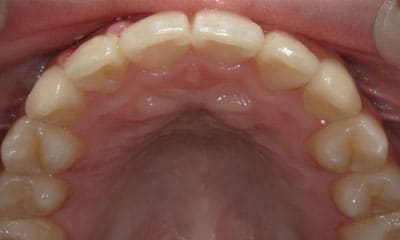

● 歯根が折れ保存不可の歯を抜歯して、そのスペースに八重歯を並べた症例

藤沢デンタルオフィスの虫歯や破折で抜歯後の部分矯正